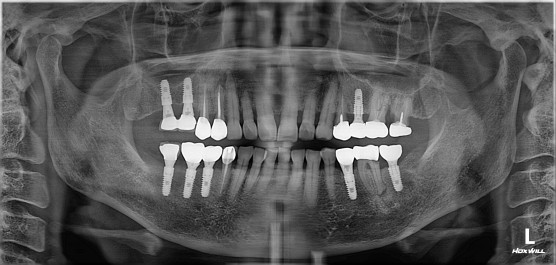

치근단 절제술 및 뼈 이식

치료 기간 2024. 02. 17

cc. 오른쪽 위 잇몸이 부었다고 내원하심.

#14 뿌리 밑 염증, fistula 발견